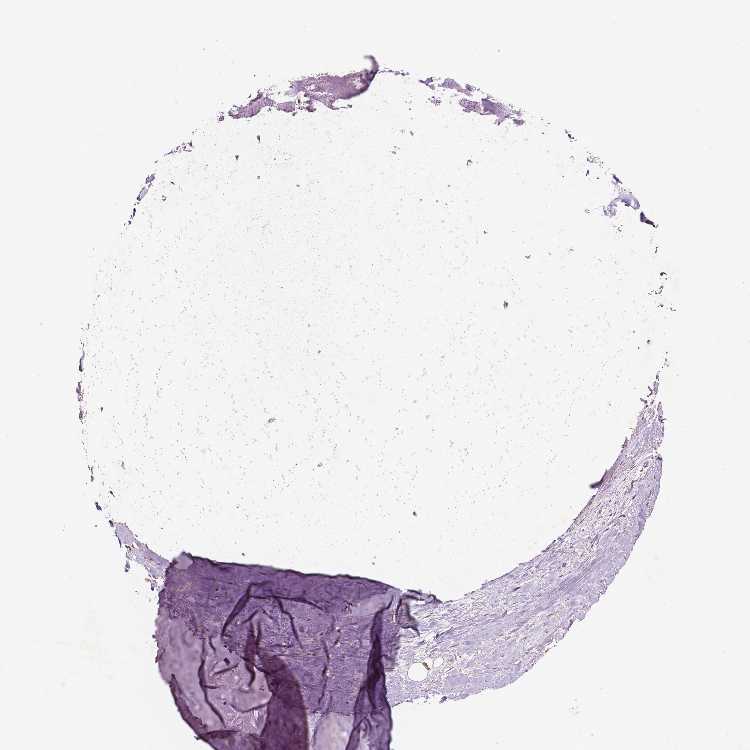

SOFT TISSUE 1 - Antibody stainingi

Antibody staining in the annotated cell types in the current human tissue is reported as not detected, low, medium, or high, based on conventional immunohistochemistry profiling in selected tissues. This score is based on the combination of the staining intensity and fraction of stained cells.

Each image is clickable and will lead to virtual microscopy that enables deeper exploration of all samples and also displays staining intensity scores, fraction scores and subcellular localization as well as patient and tissue information for each sample.

Antibody HPA068009

Chondrocytes Medium

Fibroblasts Low

SOFT TISSUE 2 - Antibody stainingi

Peripheral nerve Not detected